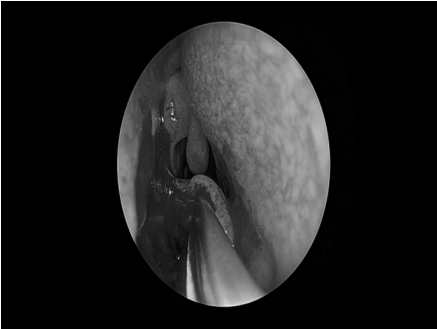

耳内镜检查:分泌性中耳炎(右)

电子喉镜检查:鼻息肉(双)

双耳鼓膜完整,右侧鼓膜内陷明显,右侧鼓室可见积液